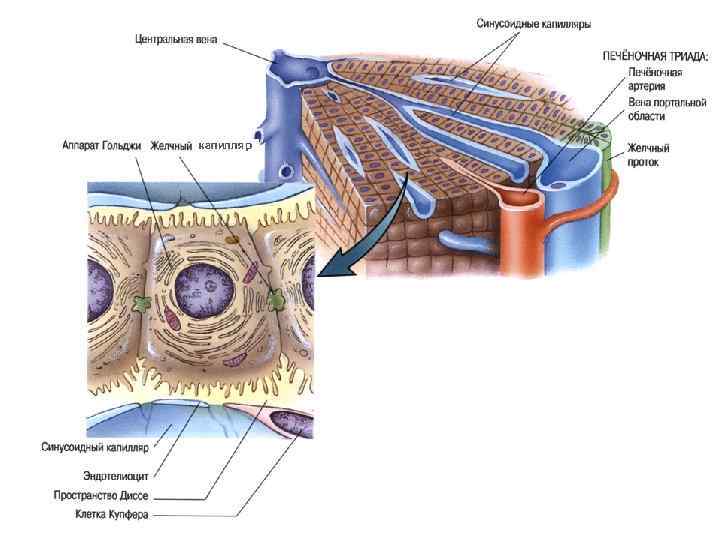

Поры в эндотелии синусоидных капилляров

1 - внутридольковый синусоидный капилляр, 2 - эндотеиальная клетка, 3 - поры в эндотелии, 4 - звездчатый макрофаг, 5 - перисинусоидальное пространство Диссе, 6 - ретикулярные волокна, 7 - микроворсинки гепатоцитов, 8 - гепатоциты, 9 - желчный капилляр, 10 - перисинусоидальный липоциты (клетки Ито), 11 - жировые включения, 12 - эритроциты

Желчный капилляр Плотный контакт Десмосома Звездчатый макрофаг (Купферовская клетка) Эндотелиоцит Перисинусоидальное пространство Диссе Ретикулярное волокно Липоцит Ямочная клетка Плотный контакт Ретикулярное волокно

Ретикулярные волокна

Синусоидный капилляр печени 1 -эндотелий с порами, 2 - пространство Диссе

Желчный капилляр печени 1 - ядро, 2 -митохондрия, 3 - лизосома с желчными пигментами, 4 - желчный капилляр

Желчный капилляр

Обменные и секреторные процессы в гепатоцитах